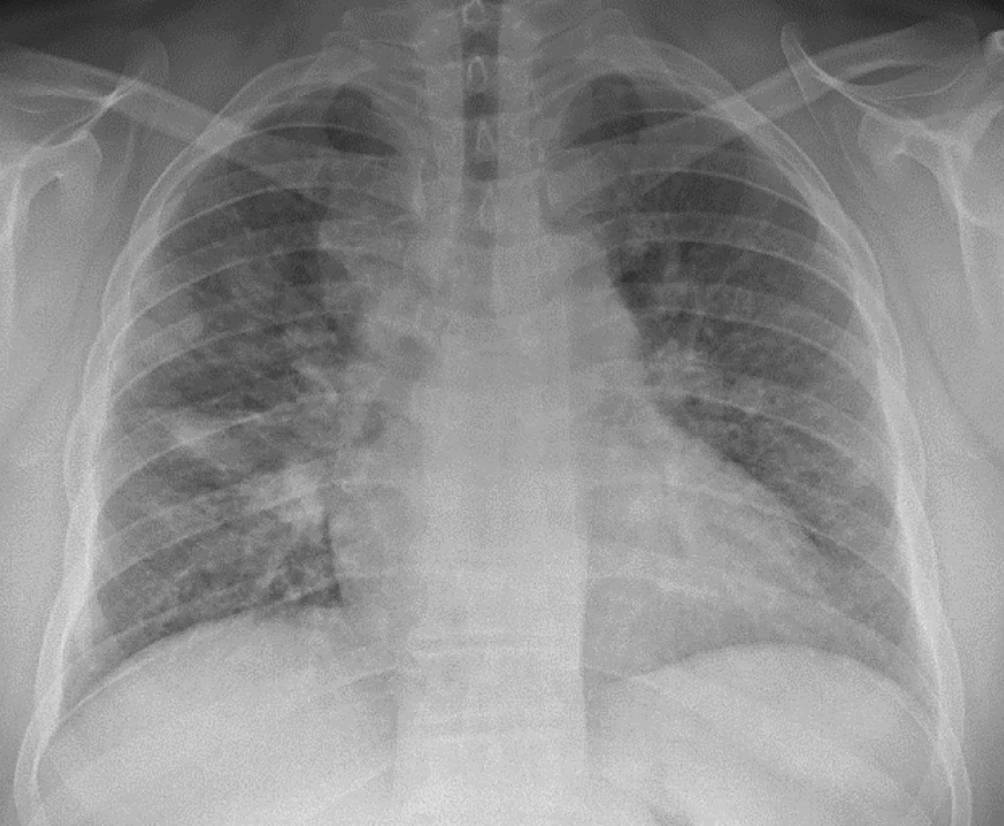

Vorwegzunehmen ist, dass die sichere Diagnose der Sarkoidose einen histologischen Nachweis der granulomatösen Entzündung und den Ausschluss anderer Ursachen von Granulomen, beispielsweise Tuberkulose oder Vaskulitiden, erfordert. Hilfreich dabei ist die Bildgebung: Während die Thoraxröntgenuntersuchung zwar durch die mediastinale und hiläre Lymphadenopathie und Parenchymveränderungen (Abb. 2) auffällig sein kann, ist die Computertomographie des Thorax (CT) wesentlich genauer und kann auch geringere Krankheitsausprägungen sicher detektieren (Abb. 3). Die 18F‑FDG-PET/CT hat sich weiters bewährt, extrathorakalen Befall darzustellen, geeignete Biopsiestellen zu identifizieren und in komplexen Fällen das Krankheitsansprechen zu kontrollieren (Abb. 4).

Abb. 2

Thoraxröntgenuntersuchung bei Sarkoidose, klassifiziert als Scadding II. Man sieht einerseits vergrößerte mediastinale und hiläre Lymphknoten, andererseits fleckige Parenchymauffälligkeiten